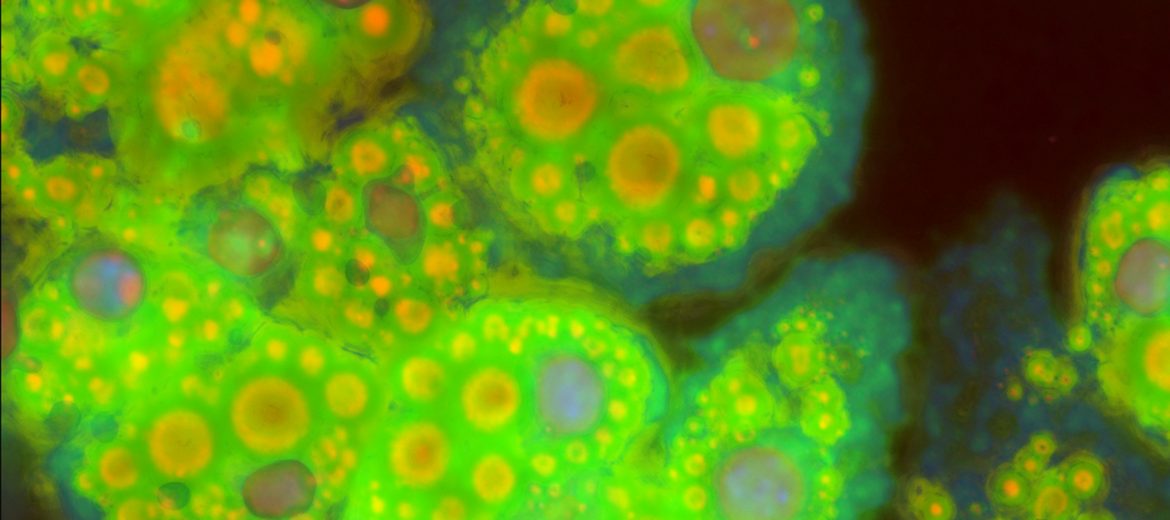

Cultured fat cells: compound image derived from light, fluorescent and TIRF microscopy and probability mapping. The GLUT4 and TUSC5 at the cell surface are seen as blue-green particles around the edge of the cells.

The researchers used high-end fluorescence imaging techniques in the AMMRF (now Microscopy Australia) at USyd. They discovered that a protein called TUSC5 resides in the GLUT4 storage vesicles and helps insulin-stimulated GLUT4 translocation to the membrane. Further, they found that TUSC5 was lost in insulin resistance suggesting that it has a role in this condition and could be investigated as a drug target.